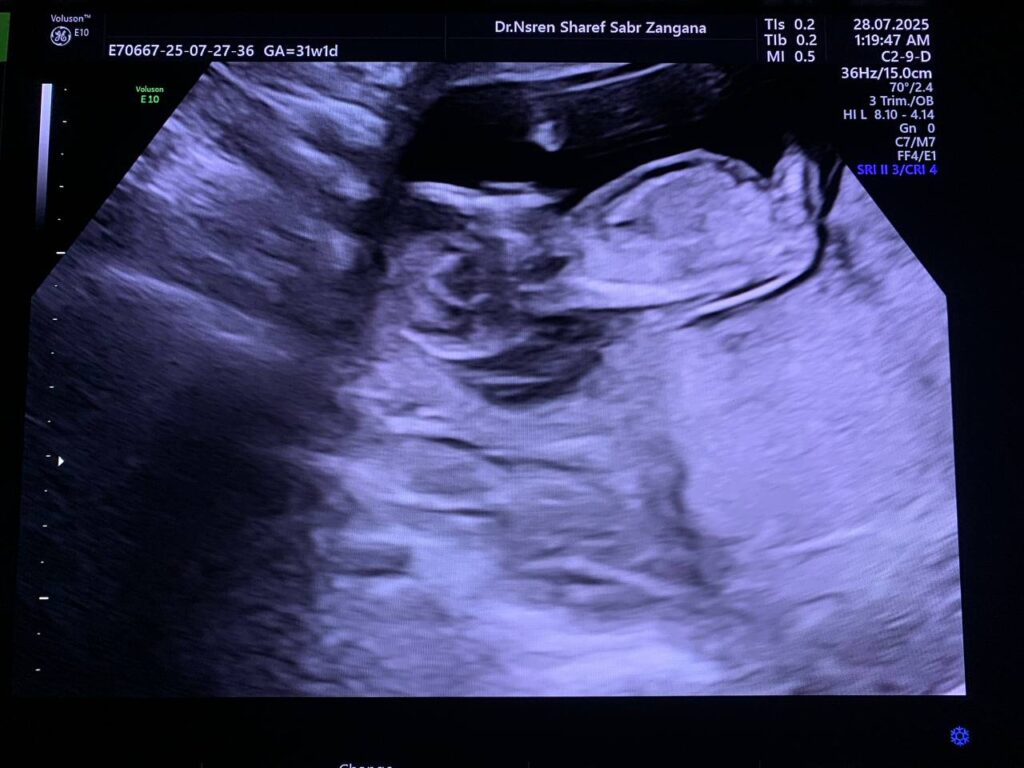

Diffuse edema with Increase nuchal translucency 6.7mm , hypoplastic nasal bone , picture mostly of hydrops fetalis with chromosomal anomaly , please for further study

CRL= 12w+6d